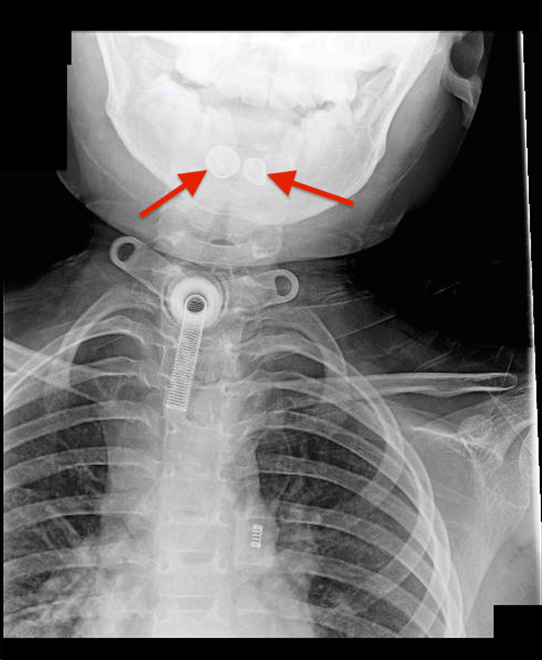

Figure 2: An eight-year-old boy with two radiopaque densities incidentally found on modified barium swallow study. Findings: Two radiopaque objects (red arrows) at the level of the hypopharynx near the cervical esophagus. Technique: Anteriorposterior neck soft tissue plain radiograph.

An eight-year-old neurologically devastated boy residing in a specialized nursing home for medically frail children was brought into the emergency department for evaluation of two foreign bodies found incidentally on modified barium swallow study (MBSS). The patient has a history of posterior fossa arteriovenous malformation (AVM) rupture causing large left sided cerebellar hemorrhage that left the patient gastrostomy tube, tracheostomy, and ventilator dependent. Since the AVM rupture, the patient experienced continuous bruxism and tongue biting that required him to wear a mouth guard. The swallow study was performed for evaluation of swallowing prior to advancing his oral intake. Oddly, the patient had been completely asymptomatic with no changes in his ventilator requirements despite the impaction of these foreign bodies. He had been tolerating his gastrostomy tube feeds and did not seem like he was in pain. X-ray of the neck soft tissue lateral view (Figure 1) and anteroposterior view (Figure 2) showed two radiopaque densities ~5–10 mm each, which have the appearance of teeth within the hypopharynx/vallecula at the level of C3 and C4. Consultation to otorhinolaryngology team was initiated. Patient was scheduled for removal in the operating room under general endotracheal anesthesia. The foreign objects were removed under direct visualization with direct laryngoscopy and forceps. The remainder of the laryngoscopic examination was normal. Pathology was consistent with two irregularly shaped shiny golden metallic dental crowns measuring 1.0x0.6x0.6 cm and 1.1x0.8x0.6 cm. A photograph of the dental crowns was taken (Figure 3). It is unclear when our patient lost both his crowns and how long they were in his hypopharynx. However, on chart review, a lateral X-ray of the skull (Figure 4) performed eight months prior to discovery of the foreign bodies on the MBSS showed the two radiographic densities in the same place. This indicates that these dental crowns may have been impacted in the patient's hypopharynx for over eight months. The identification of these two radiographic densities was missed on the initial skull X-ray read. Additionally, a dental consult and examination was performed on the same day as the skull X-ray, which failed to detect the missing dental crowns but showed that his mouth-guard was loose and that teeth 7–10 and 23–26 were mobile/loose.